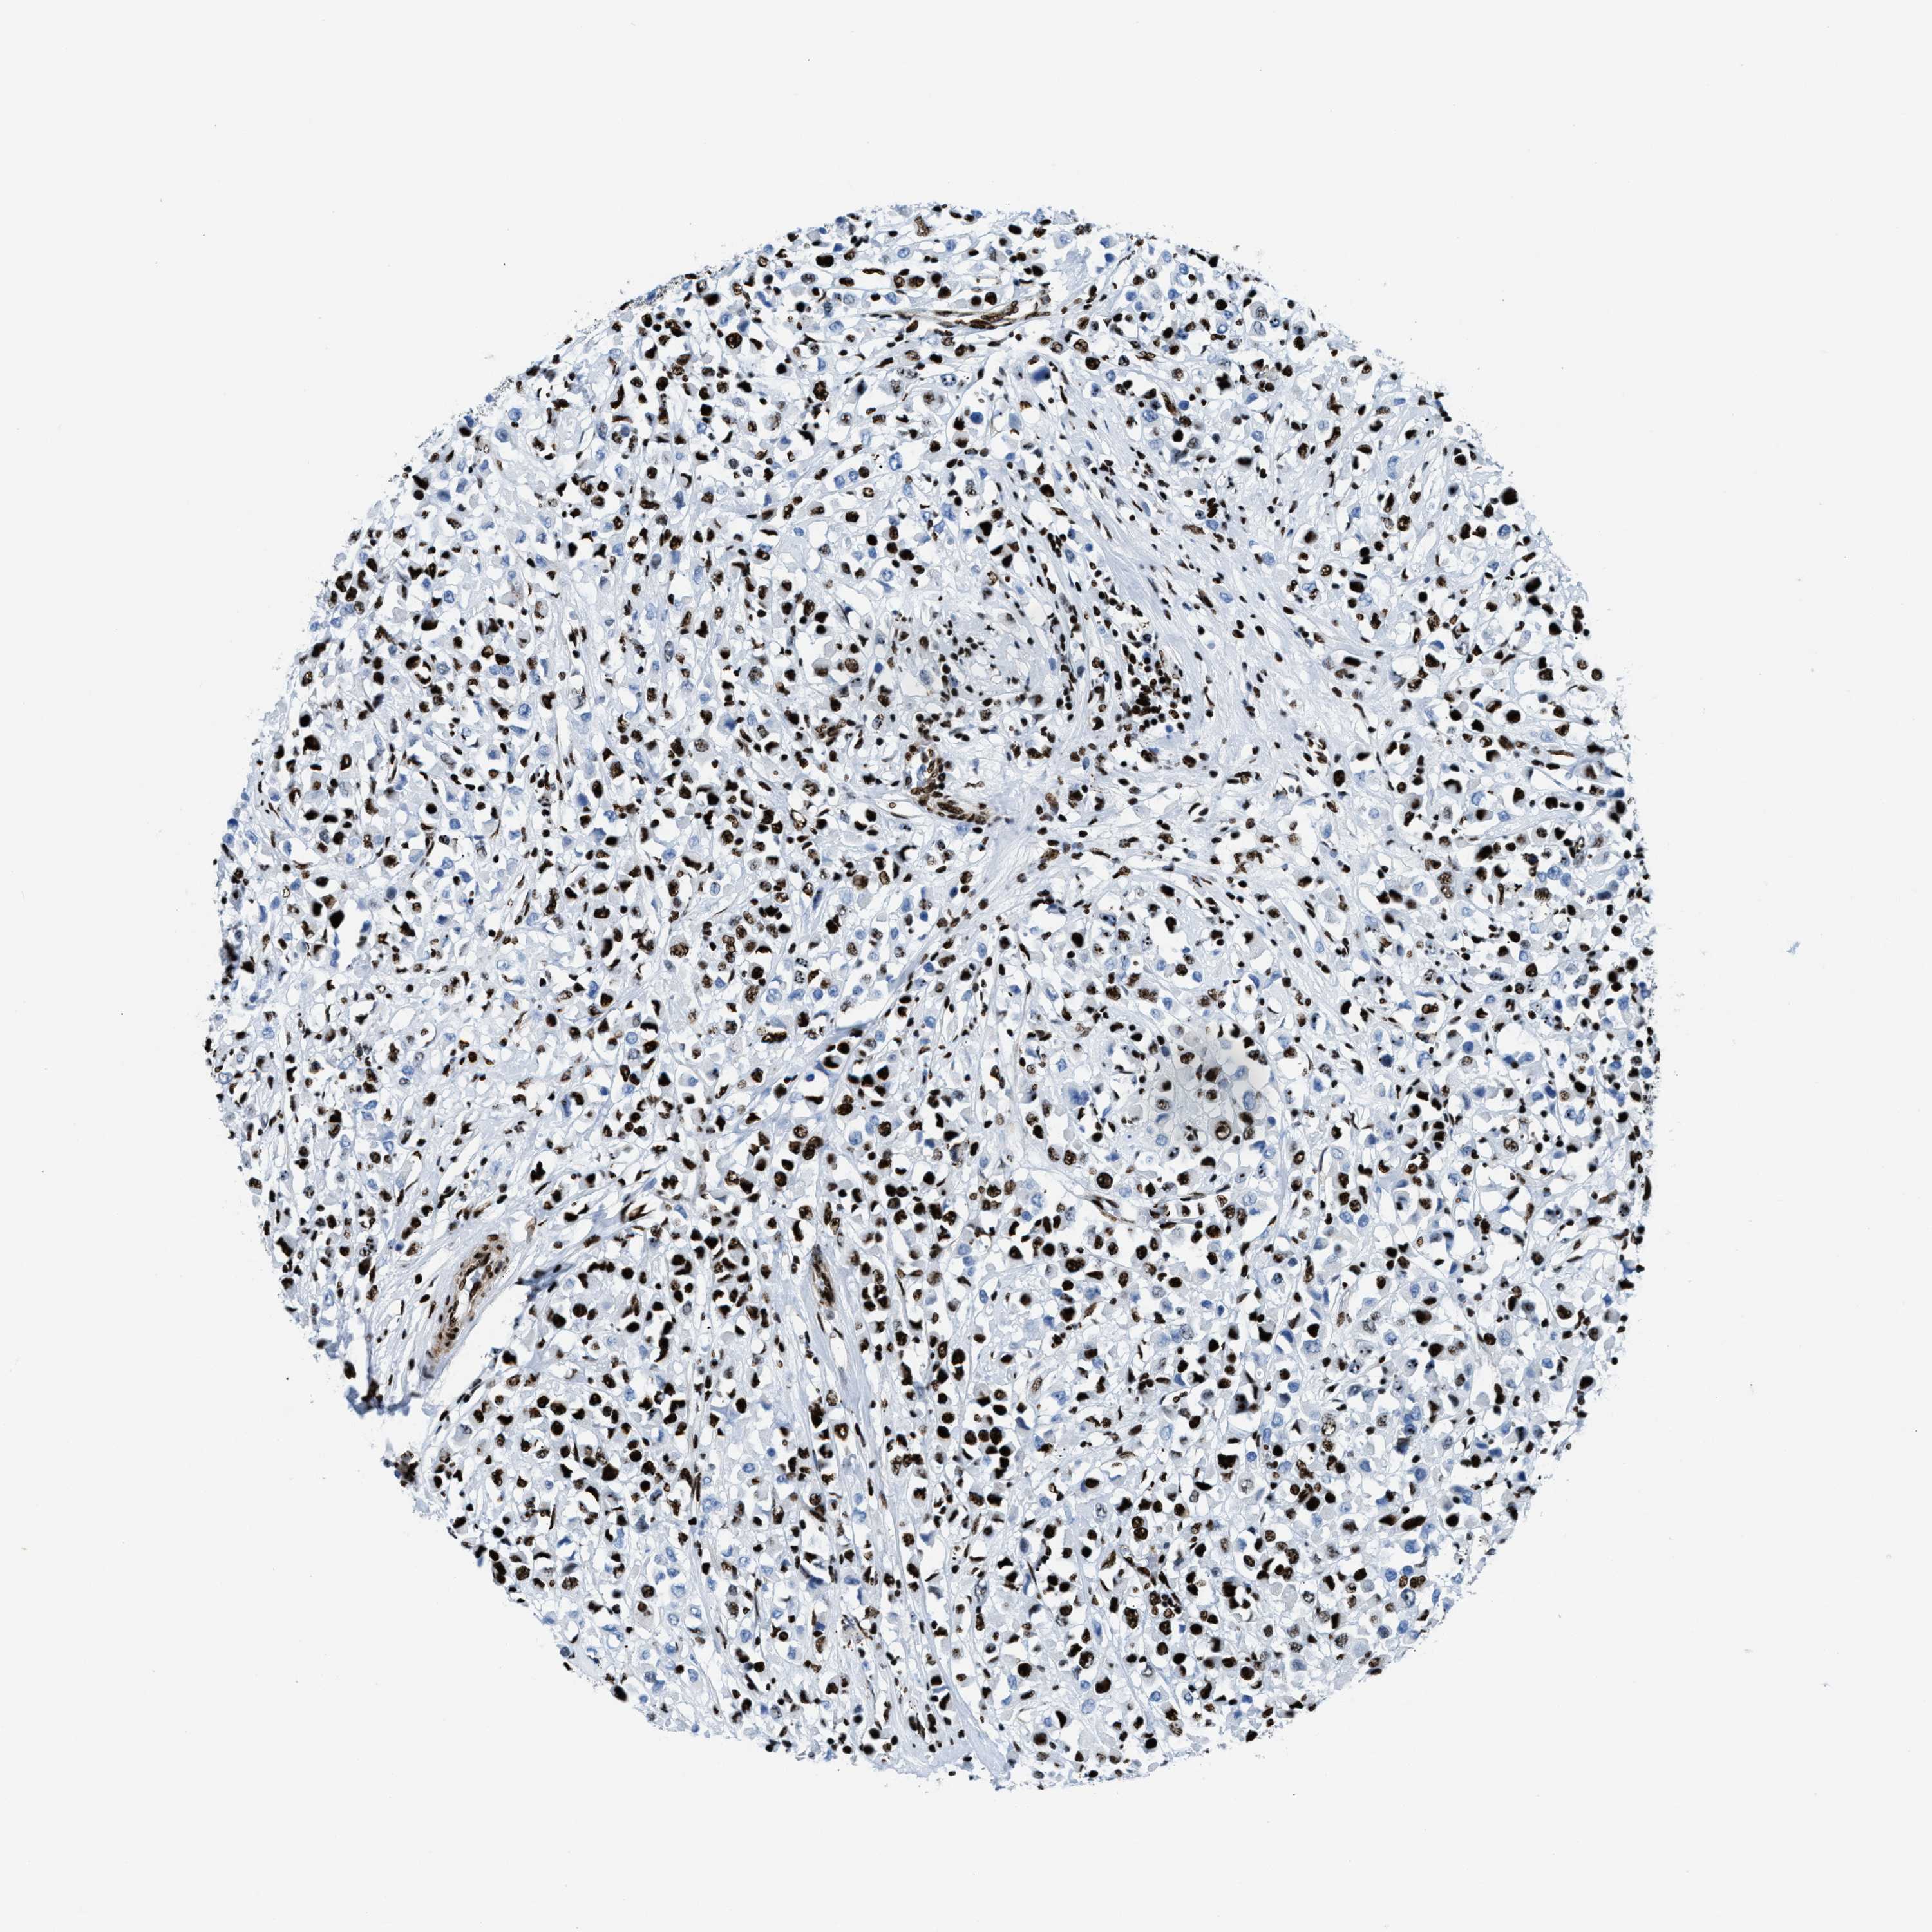

CANCER BREAST CANCER Show tissue menu

BRCA TCGA BRCA VALIDATION PROTEIN EXPRESSION

Breast cancer

Human cancer